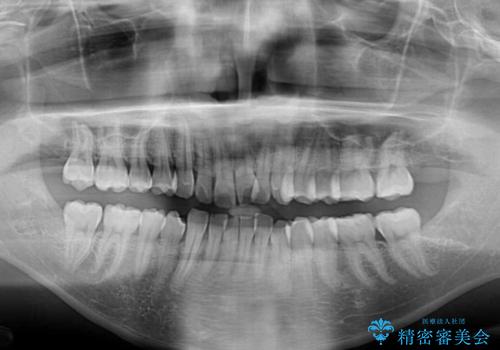

- 前歯のデコボコを治したいとのことで来院された患者様です。

上下顎ともに歯列全体の後方移動とIPR(歯と歯の間を削る)によってデコボコが解消するように設計し、インビザラインにより治療を行うこととしました。